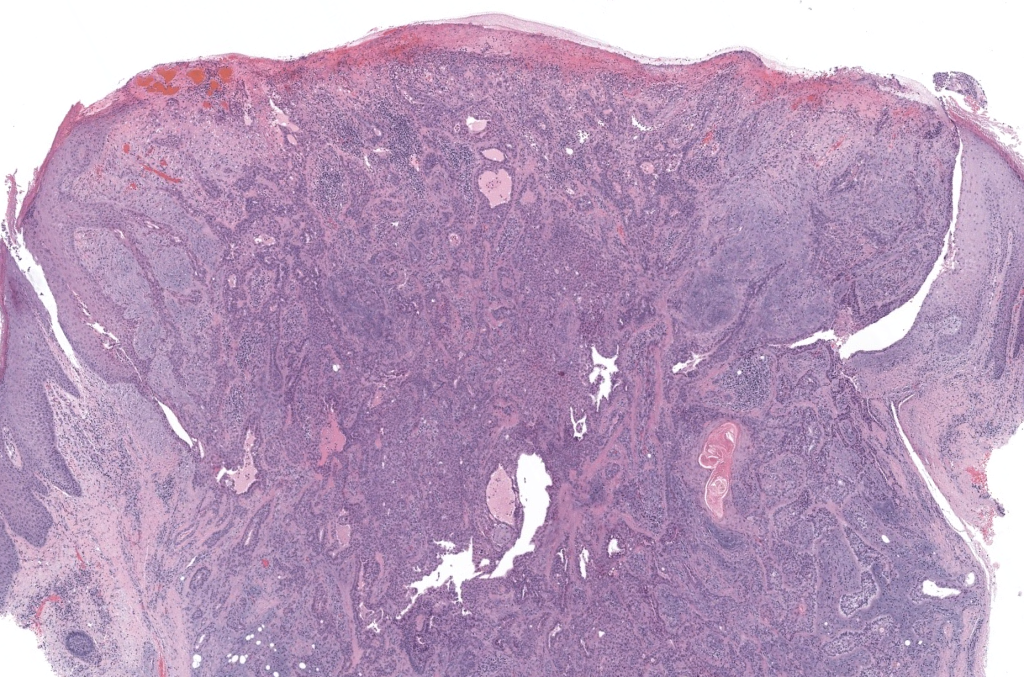

- Nombres: Tumor mixto cutáneo, Siringoma condroide, Adenoma pleomórfico de la piel (por su similitud histológica con el adenoma pleomorfo de glándulas salivales) Obaidat 2007,Wan 2018

- Historia: Probablemente descrito por Nasse en 1892 como tumor mixto de piel. El término “Siringoma condroide” fue propuesto por Hirsch y Helwig en 1961 en una serie clásica de casos.Kallam 2013 (citando Hirsch & Helwig)